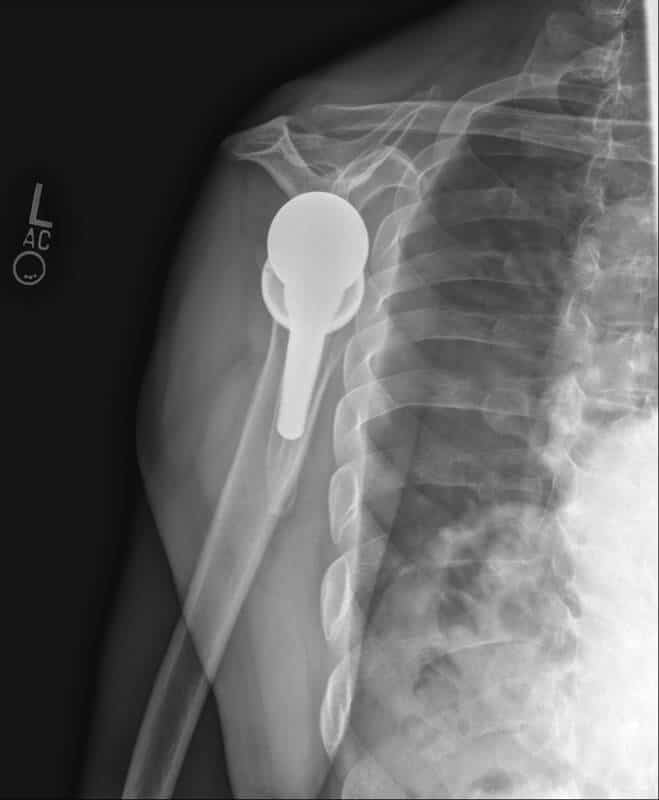

American Shoulder and Elbow Surgeons > Stryker/Wright/Tornier, Perforrm

Stryker/Wright/Tornier, Perforrm